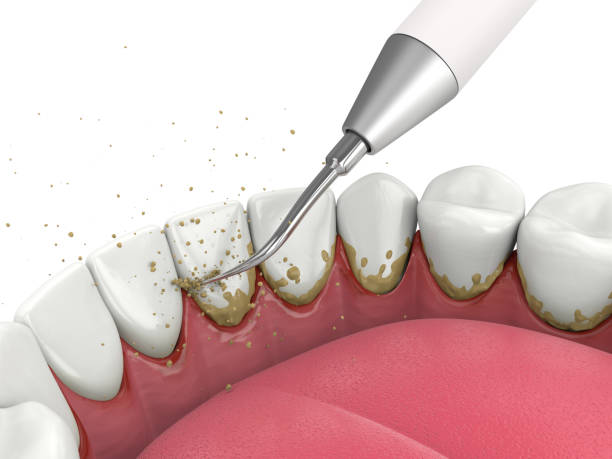

단계에 따라 치료하는 방법이 다른데, 만성 단순 변연부치주염은 스케일링(치석 제거)을 통해 치태와 치석을 제거하여 치료합니다. 만성 단순/복합 치주염의 경우에는 스켈링을 비롯하여 잇몸에 부분적으로 마취하여 염증부위를 긁어내는 식의 추가적으로 치료가 필요하며, 문제가 되는 치주낭 부분을 제거한 후 건강한 조직이 치아에 붙도록 유도하는 치료를 하기도 합니다. 만약 치주염이 심하다면 잇몸을 절개한 후 염증조직을 모두 제거하고 치조골이 재생될 수 있도록 치조골 이식수술을 시행하기도 하며, 항생제를 처방하고 치주낭부위에 항생 연고를 주입하기도 하며 느슨해진 치아를 고정하여 빠지지 않도록 치료합니다. 이렇게 노력을 기울였는데도 불구하고 계속 악화된다면 결국 치아를 상실할 수밖에 없습니다.